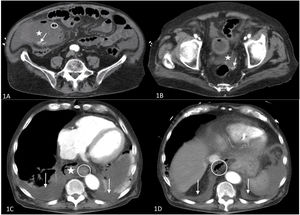

An urgent chest-abdomen computed tomography scan was performed, showing acute emphysematous cholecystitis (Fig. 1A) complicated with probable bilioperitoneum (Fig. 1B). An incidental finding was bilateral pleural effusion and collections in the mediastinum containing air, indicative of NM (Fig. 1C), and air in the retroperitoneum extending to the mediastinum (Fig. 1D). No esophageal ruptures were identified, which, together with the absence of subcutaneous emphysema, allowed us to reasonably rule out esophageal perforation.

A and B: Abdominal CT 1A: Enlarged gallbladder (asterisk) containing lithiasis (arrow) and free gas in the wall of the gallbladder (circled), indicative of emphysematous cholecystitis. 1B: Pouch of Douglas containing free fluid (asterisk) and lithiasis (arrow), showing bilioperitoneum. C and D: Chest CT. 1C: Upper chest slices; mediastinal collection containing air (asterisk); esophagus (circled); bilateral pleural effusion (arrows). 1D: Thoracoabdominal sections; diaphragmatic domes (arrow); retroperitoneal air (circled) progressing to the chest.